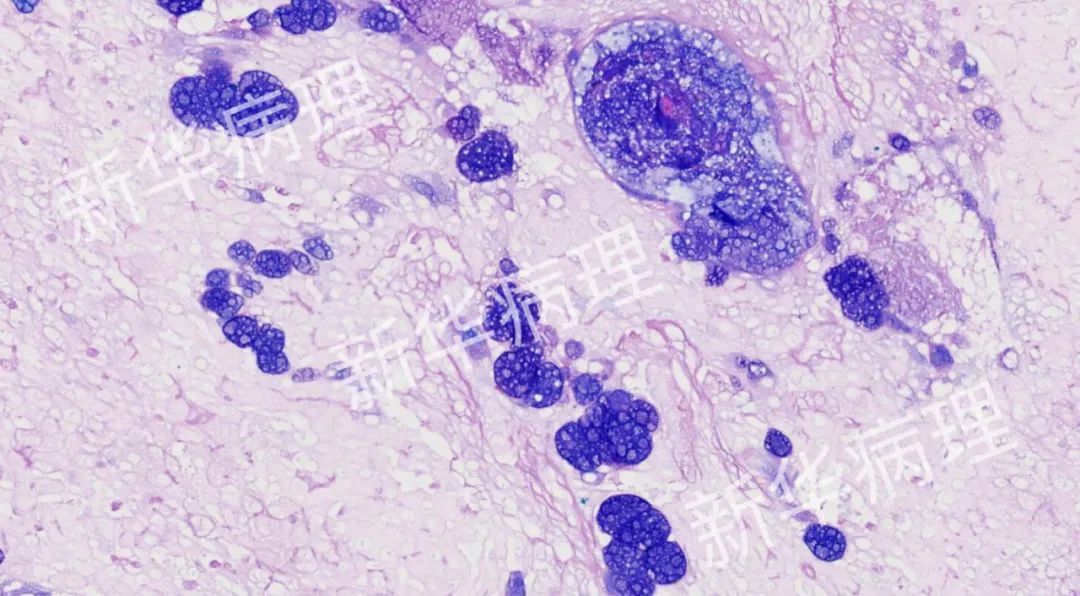

肺部感染的新生隐球菌(PAS染色)